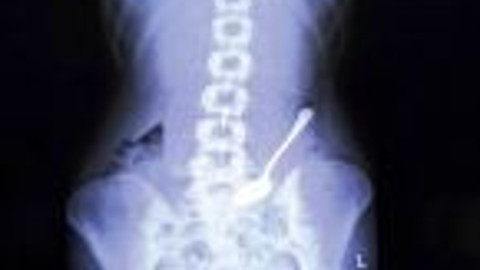

Çatal

Vücutlarından çıkanlar sizleri şoke edecek Galerinin tamamı için tıklayınız Çataldan paraya yüzükten çiviye İnsanların vücutlarına giren şeyler sizi çok şaşırtacak..